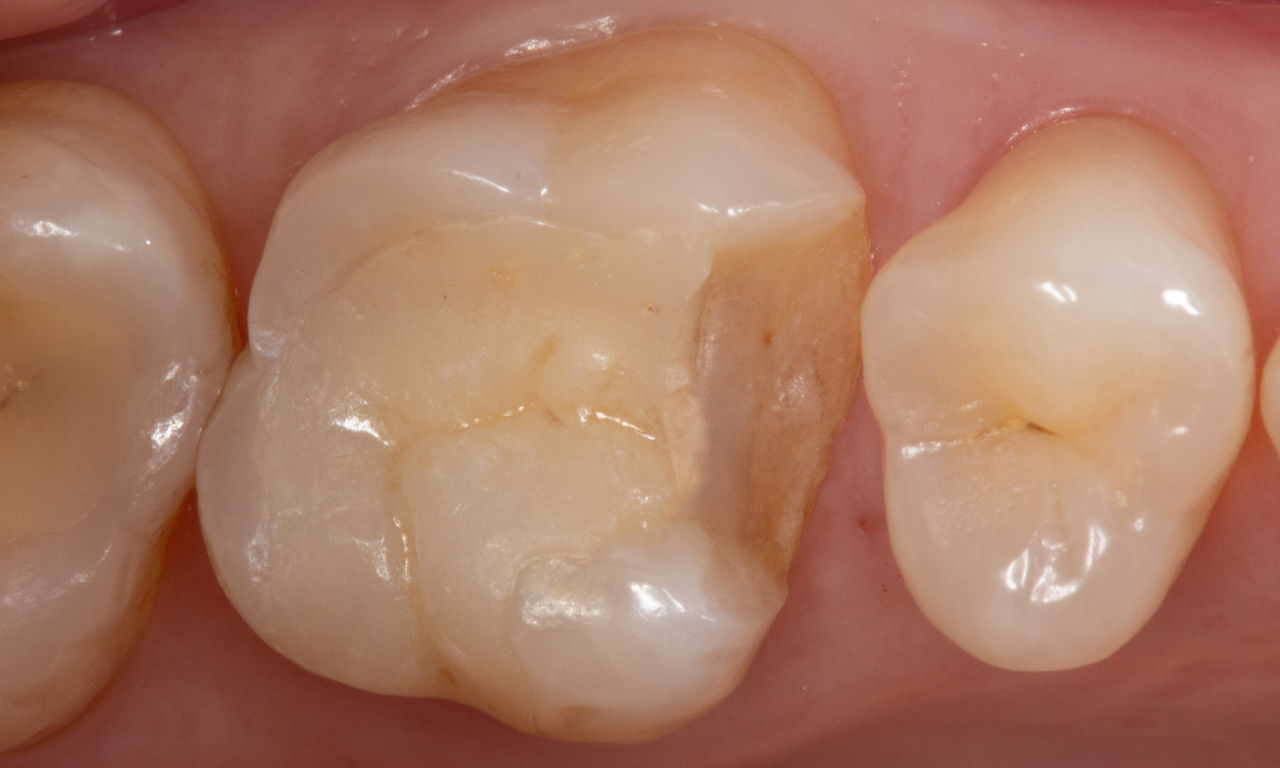

Before: First upper molar had been restored with an extensive yet insufficient composite filling that already showed visible fractures.

After: Chairside-fabricated restoration made from an advanced lithium disilicate ceramic, CEREC Tessera.